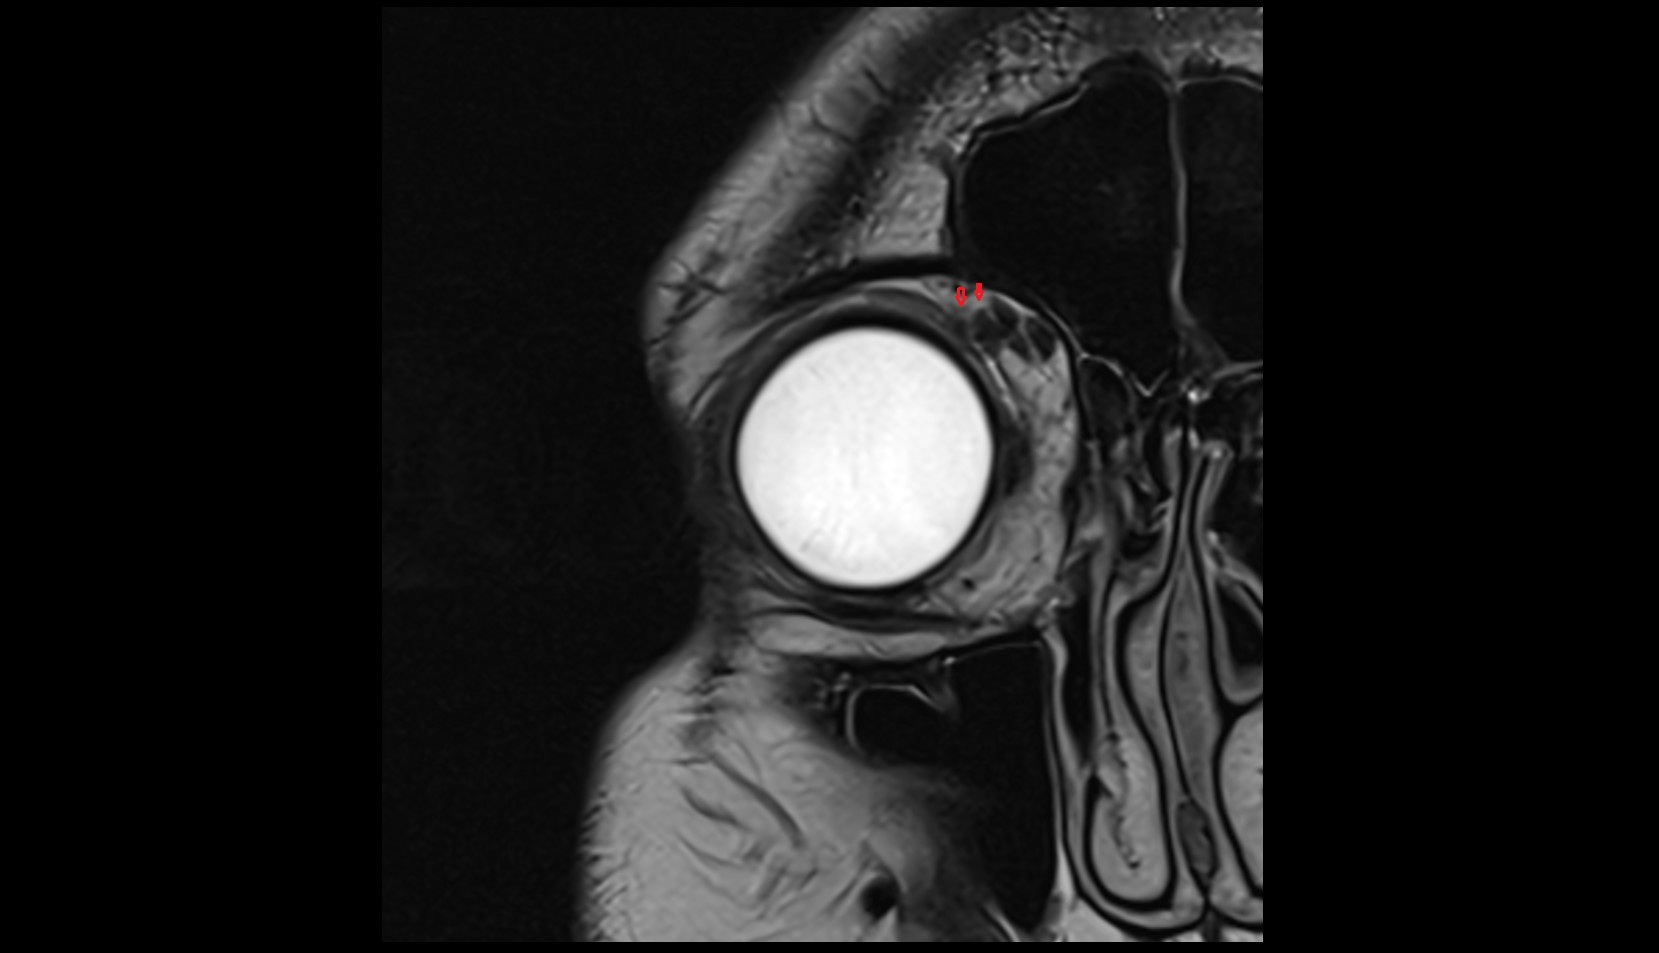

- Orbital part of optic nerve

- Retrobulbar fat

- Optic nerve sheath

- Subarachnoid space of optic nerve

- lens of the eye

- Cornea

- Iris

- Pupil

- Anterior chamber of eyeball

- Posterior chamber of eyeball

- Vitreous chamber of eyeball

- Sclera

- Choroid

- Retina